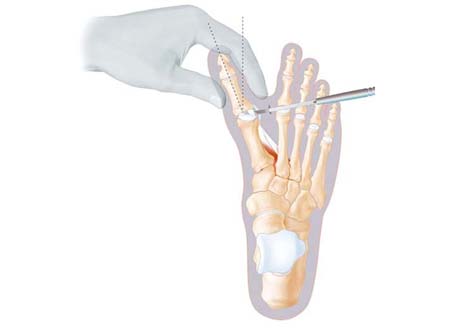

Figure 10

Small burr used to cut ball of the toe to shift it inwards

Figure 11

Instrument used to lever the ball of the toe inwards under Xray guidance, after it is cut